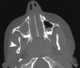

Undescended maxillary tooth

Sinonasal mass without bone changes